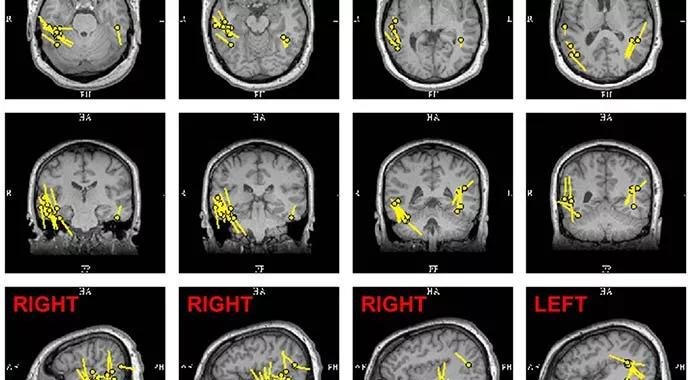

Subtraction single-photon emission computed tomography (SPECT) showed right posterior lateral temporal hyperperfusion extending to the inferior mesial occipital regions bilaterally (Figure 2). Magnetoelectroencephalography (MEG) recordings showed posterior temporal spikes on the right more than the left (Figure 3).

Figure3

Figure 3. MEG recordings showed posterior temporal spikes on the right more than left.